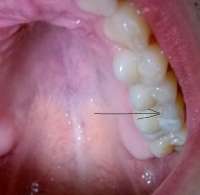

14734355806570.jpg (1325Кб, 1404x1076)

Антуаны, снова нид хелп. Я все тот же Антоний >>512791

Заделал все верхние зубы, в четверг иду ставить брекеты на "верх". Снизу остался 1 зуб с кариесом, его я удалю и вот эта вот хуйня, что я пытался нарисовать на пике выше. Под зубом 46 живет-растет НЕХ. Я оставил КТ терапевту или как там его, он посмотрел и сказал, что видимо когда то залечили мне тот зуб хуевасто, что-то осталось и вот эта хуйня развилась и по-тихоньку хуует там внутри меня. Сказала, что гарантий никаких на лечение дать не может: мб каналы не "пройдет", мб ухудшится ситуация, мб лечение не поможет и придеться удалять - очень шаткая ситуевина. В чем мой вопрос, казалось бы? А вопрос в том: что блядь делать то мне с этой хуйней? Она где то там внутри, жить не мешает, не чувствуется, не видится(ну кроме как на снимке), зуб я тот делал уже и не помню сколько лет назад. МБ 10-12. Но и она и ортодонт говорят одно и тоже: это бомба замедленного действия, может выскочить в любой момент и будет пиздец. Вроде терапевт сказала, что кость там задета этой хуергой или костная ткань. Что-то типа того.

Варианты следующие:

1. Пока есть месяц-полтора до постановки на нижнюю челюсть заняться зубов, просверлить его, положить "лекарство", временную пломбу заделать, надеяться, что пронесет и ставить брекеты. Но есть шансы, что все накроется пиздой, зуб в итоге хуй сохранишь, все мне там распидорасят и будет у меня дыра. А как же тогда брекет лепить? Слепок то делался под все зубы.

2. Нихера не трогать, ставить брекеты, а заняться через полтора года, когда систему сниму. Надеяться, что пронесет. Деньги пустить на сами брекеты, а когда уже все зубы будут как надо, ровные и тд - заниматься этой хренью. Если тогда уж удалять, то думать там - мост/имплант или что.

3. Есть еще мутный третий вариант это ходить по клиникам с этим моим КТ и спрашивать, кто возьмется мне эту херню лечить и будет уверен в результате. Но чувствую, все будут говорить, что гарантий никаких, давай неси бабки и раскрывай рот.

Встанет это все не меньше 10 тысяч, а я так вангую, что 15 точно отвалить придется и хуй бы с ним, если бы результат был, а так можно 15 отдать и в итоге получить дыру.

Грамотный анон, что делать то мне? В четверг пойду к ортодонту, скажу ему, что сказал терапевт, надо будет решение принимать какое-то. В какую сторону мне смотреть?

Аноним 09/09/16 Птн 19:52:23  514691

14734399434650.jpg (61Кб, 960x720)

14734399434661.jpg (64Кб, 960x720)

>>514662

Грамотный терапевт с микроскопом тебе нужен. На крайняк - апикальная хирургия.

пики из паблика, который чекаю. Кейс одного из докторов. Мб что-то поймешь. Сравни со своей НЕХ и вот что с ней можно сделать

Ты кажется стрелку не на тот зуб показал на своём пике. У тебя там зуб без пломбы даже. кек.

Мосты - хуйня. Избегай их. Только имплант если уж решишь удалять